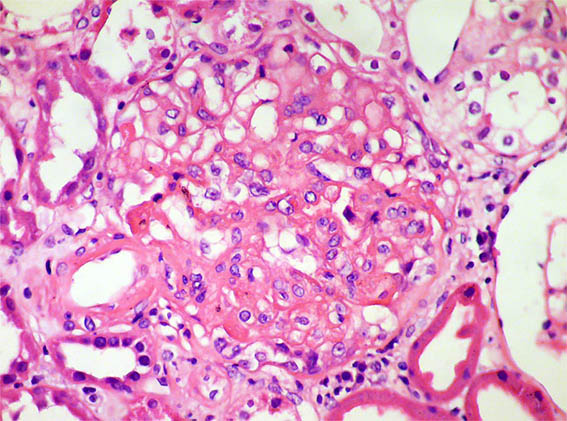

Figura 2. H&E, X400.